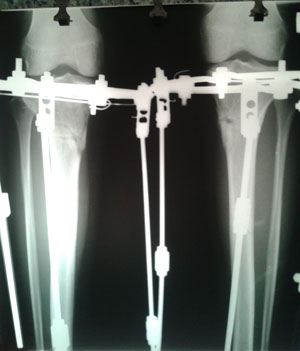

Рентген перед снятием аппаратов.

Дата операции 25.08.2014г.

Дата снятия аппаратов 07.01.2015г.

Срок лечения 132 дня.